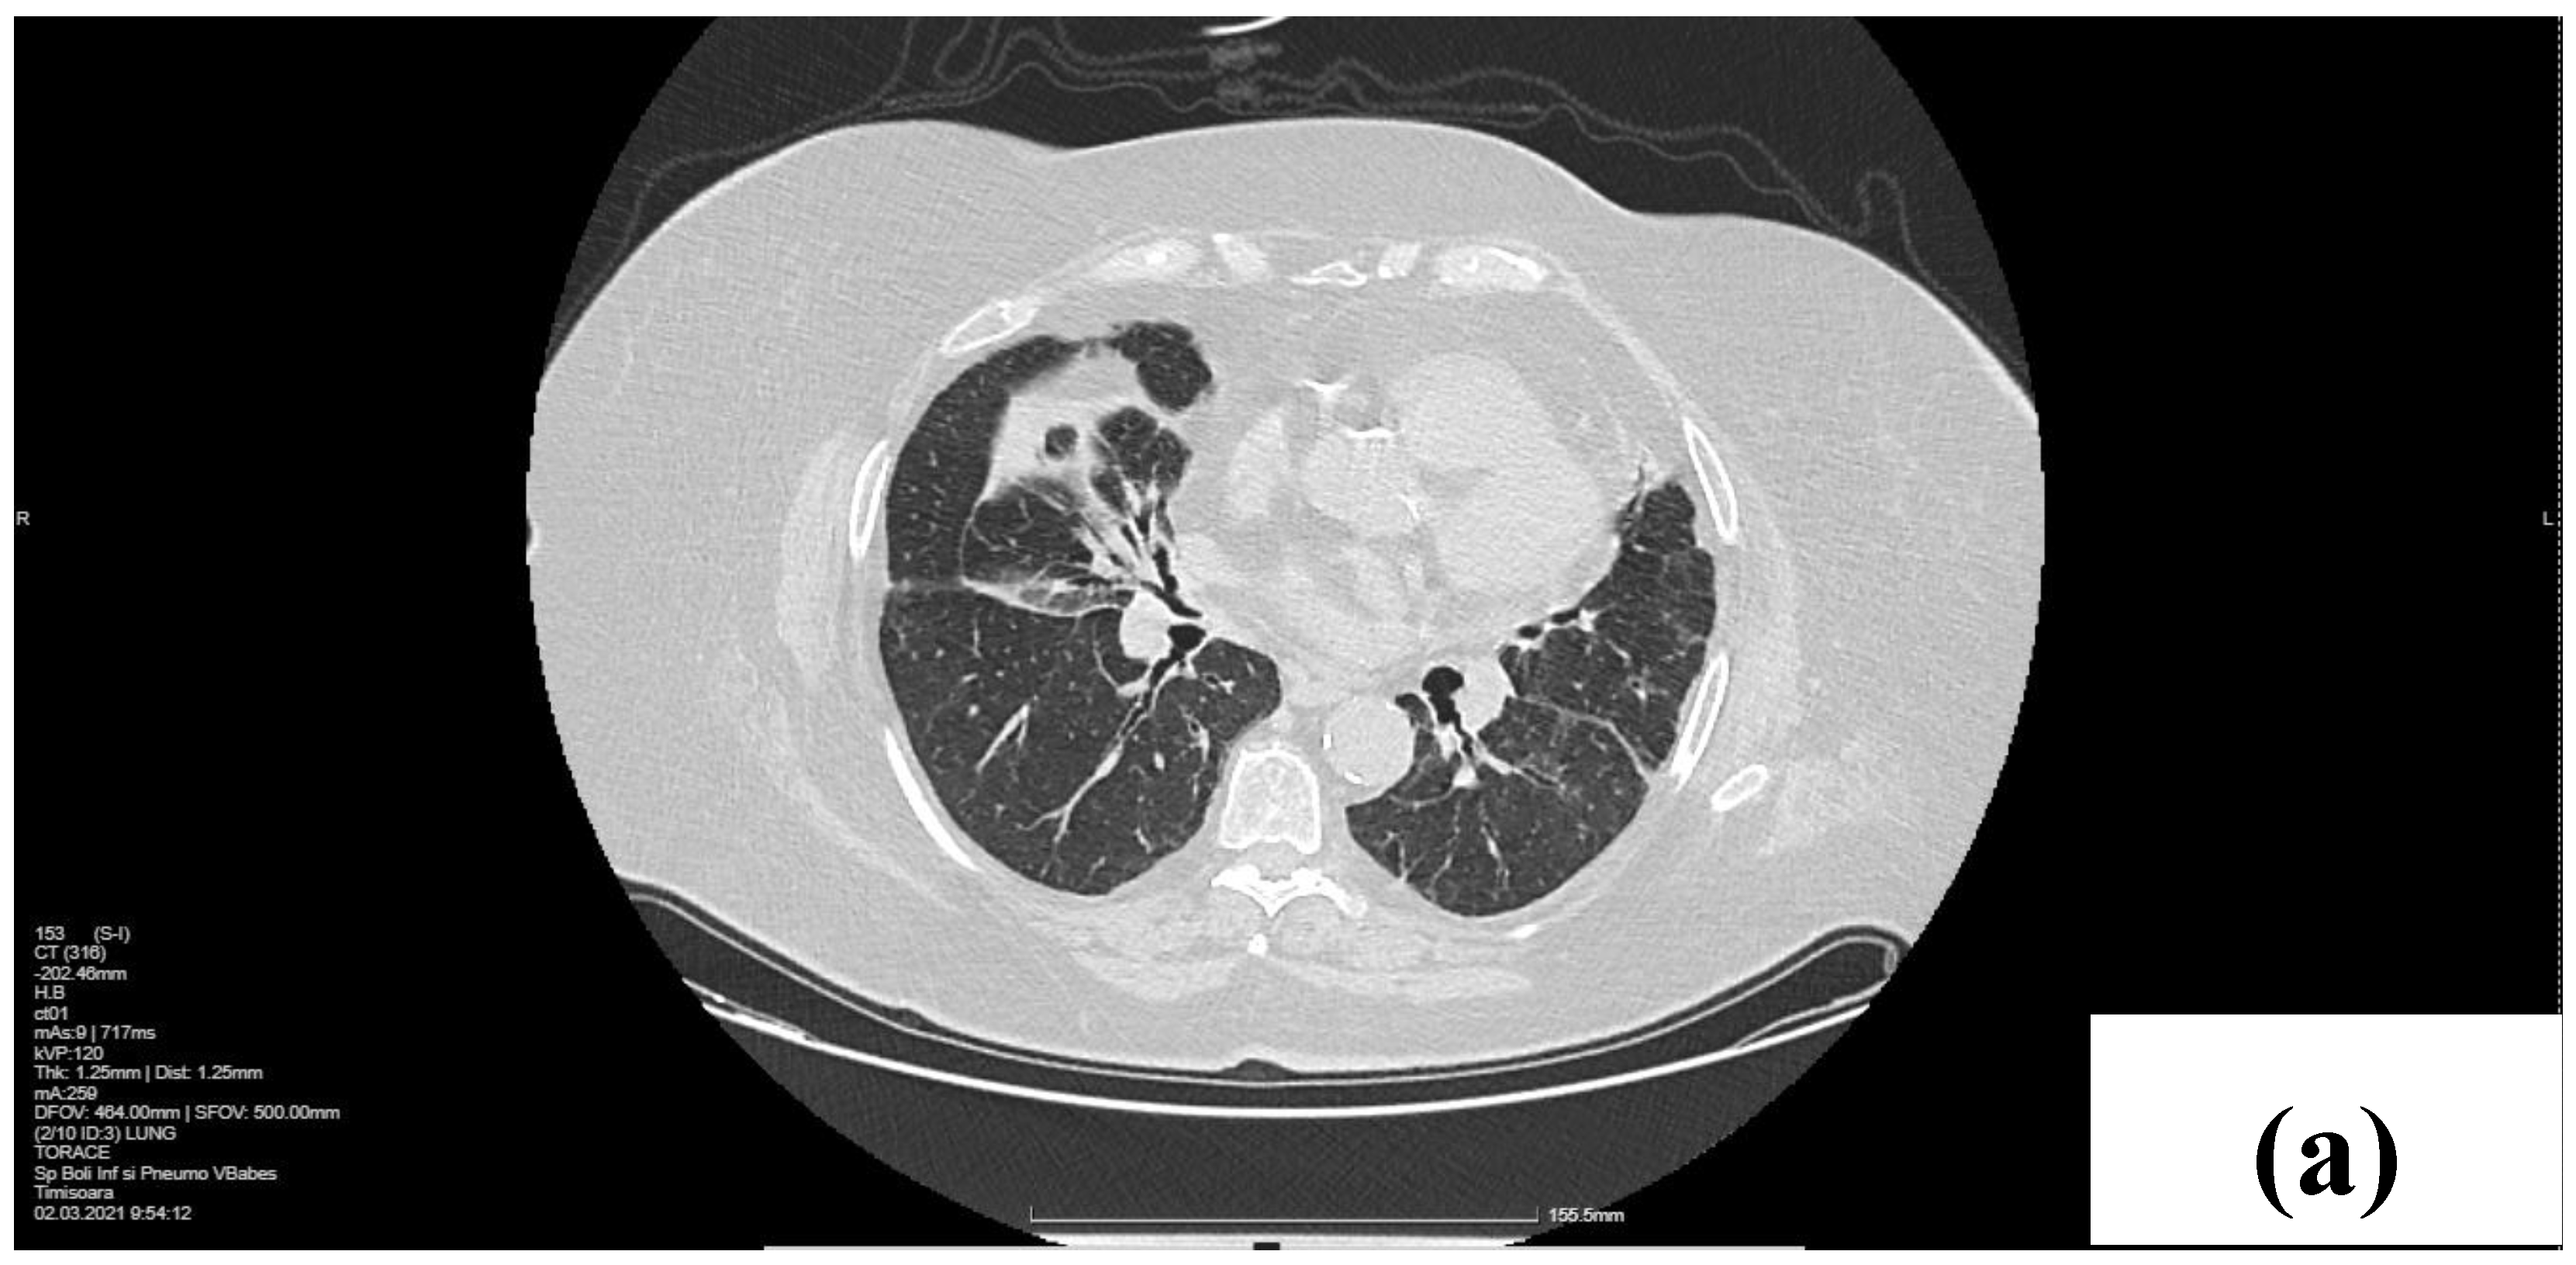

2.1. Laboratory, Radiological, and Histological Examinations

2.2. Treatment and Outcome